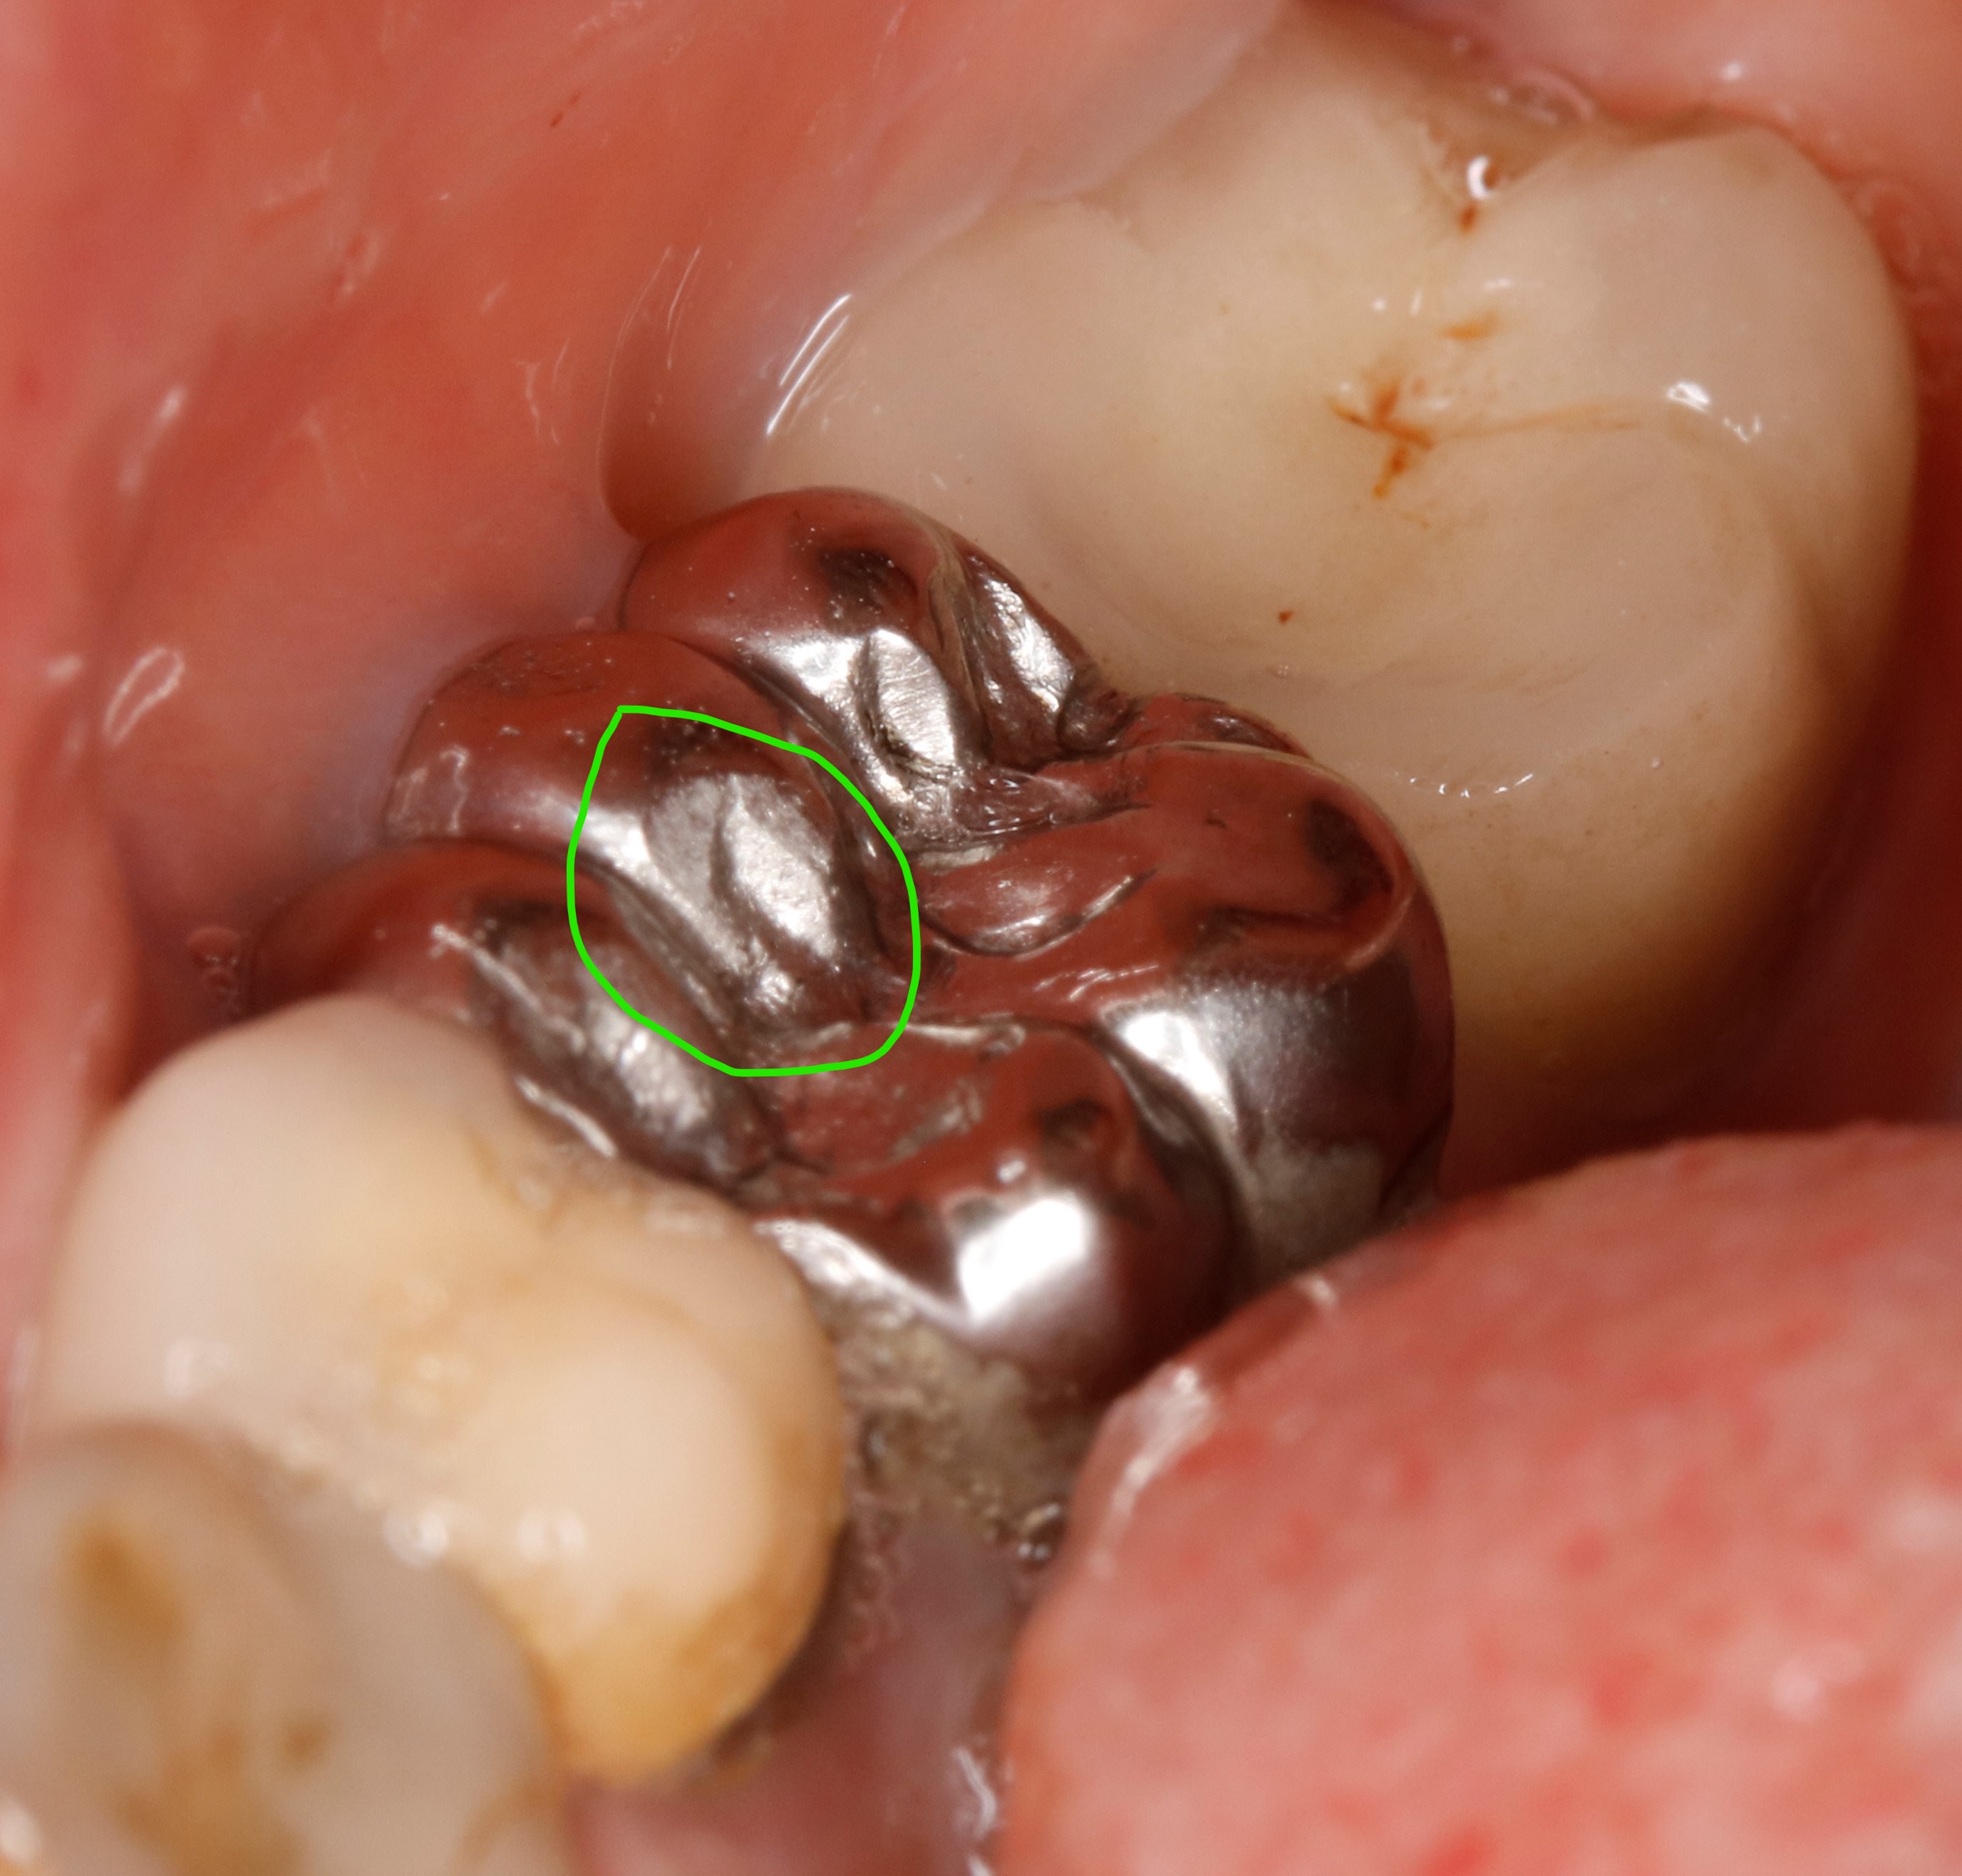

ça , c est de l usure

Inked mg 1643   copie li fjlndi - Eugenol